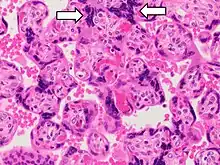

Histopathology of a chorionic villus, in a tubal pregnancy Histopathology of placenta with increased syncytial knotting of chorionic villi, with two knots pointed out.

Histopathology of placenta with increased syncytial knotting of chorionic villi, with two knots pointed out.